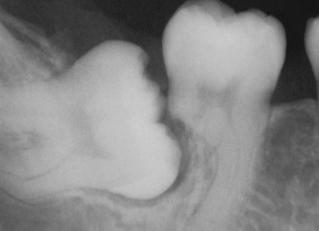

what is the dx?

dense invaginatus